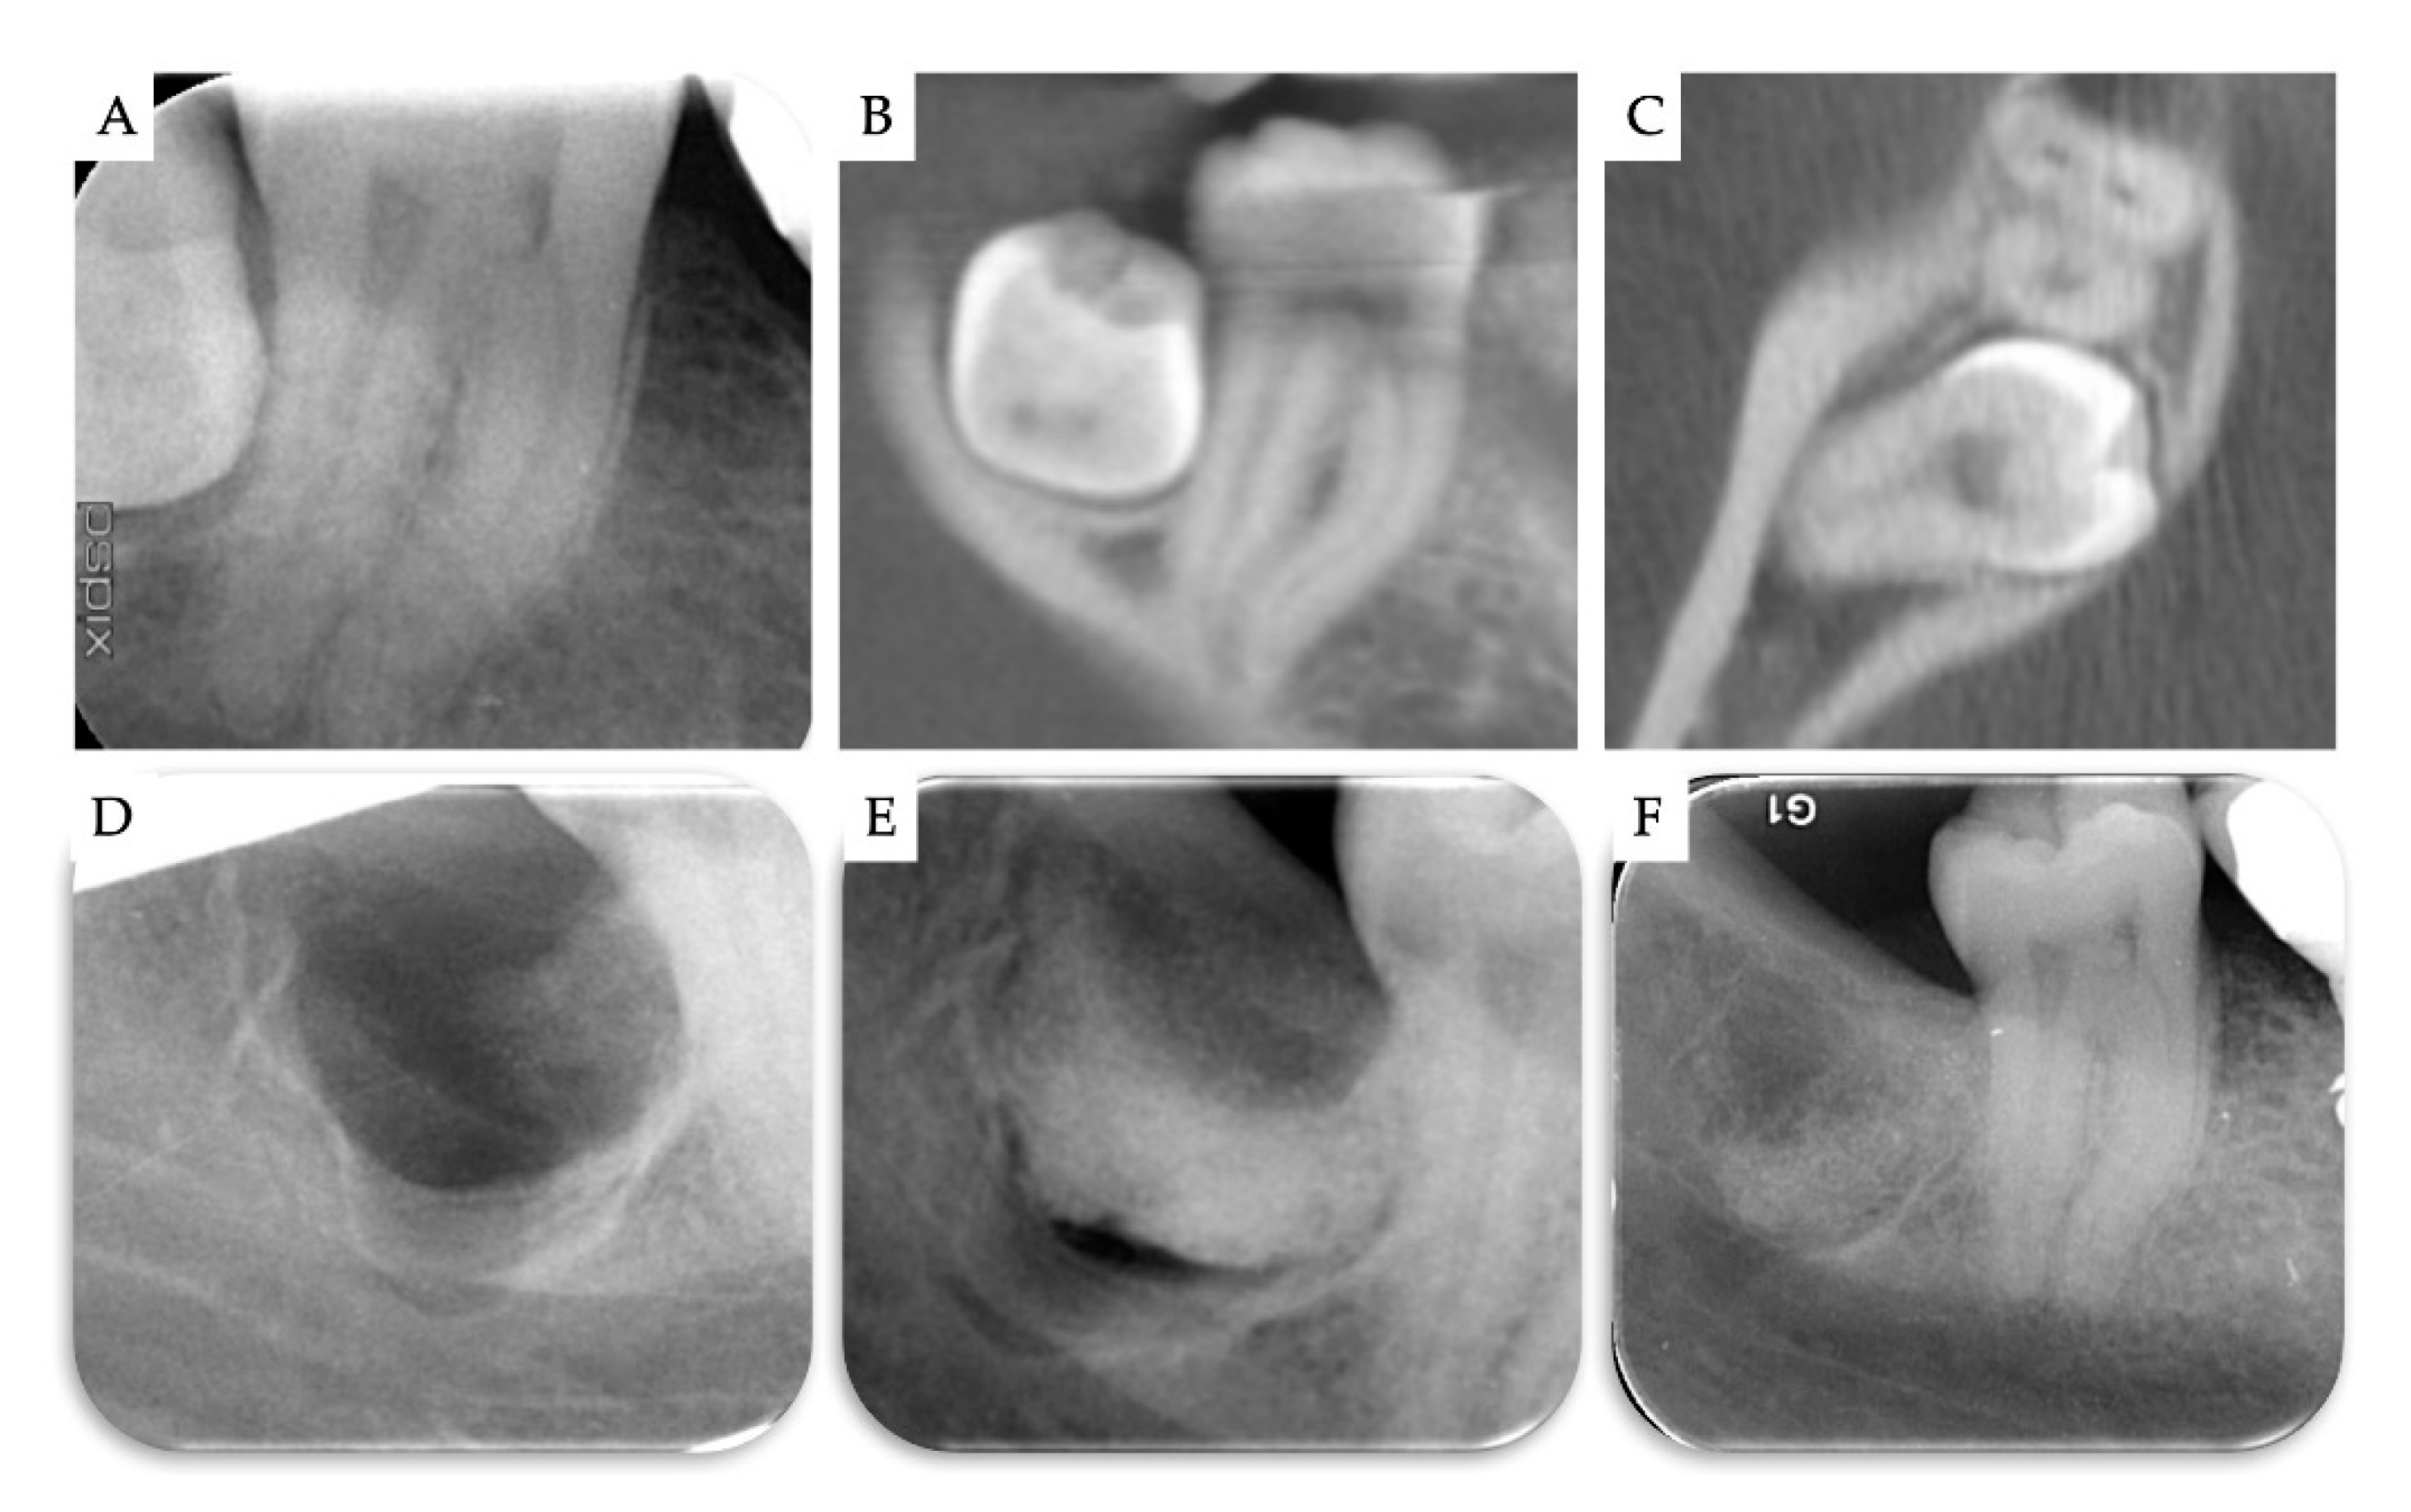

3. Results